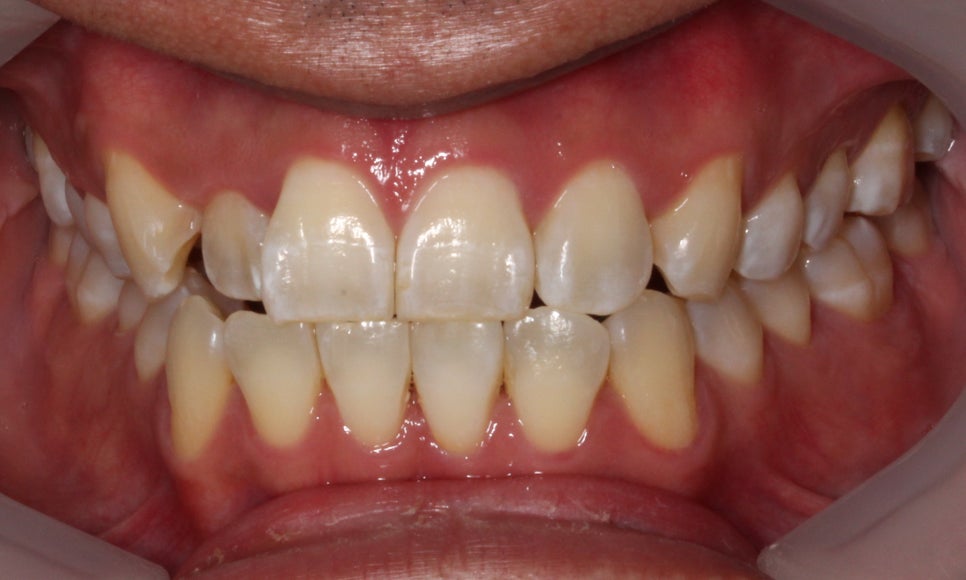

배열이 처음보다 훨씬 좋아졌습니다.

차이가 조금 더 느껴지실까요 ?^^

마찬가지로 좌 before, 우 after입니다.

이렇게 보면 훨씬 개선된 것이 눈에 띄시죠?^^

부분교정으로 진행하는 것이다 보니

전체 교정보다 완벽할 순 없지만,

환자분께서 매우 만족하셨습니다.

가장 신경 쓰여하셨던 #12 치아가

앞으로 나오면서 훨씬 가지런해지고

아래 치아 치축도 개선되면서

더욱 정돈된 이미지를 가지셔서

크게 만족하셨습니다.